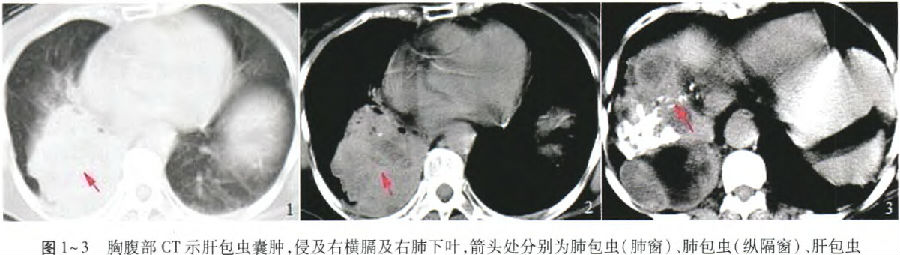

、对症等保守治疗,咯血反复发作不止。胸腹部CT示肝包虫囊肿,侵及右横膈及右肺下叶,右下肺阻塞性肺不张

(图1~3)。